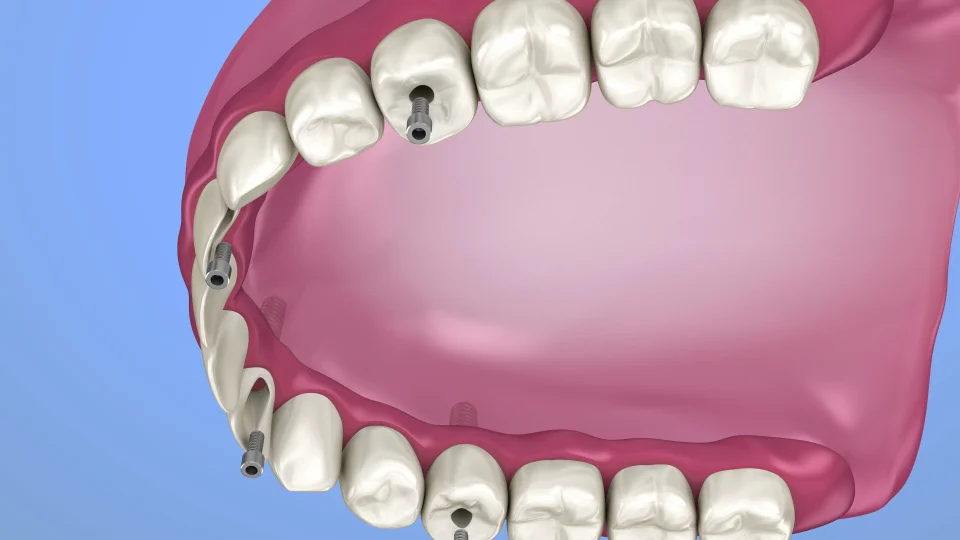

Teeth-In-An-Hour™ is an innovative technique that allows patients to receive fully functioning dental implants in just one procedure, typically completed in about an hour. Developed by Nobel Biocare, this approach involves close coordination between the restorative dentist and the oral surgeon, resulting in safer, more precise implant placement.

One key advantage is that the prosthetic teeth are created before surgery. With the aid of advanced computer-guided technology, implants are placed using a minimally invasive method, often without needing to lift the gum tissue. This means reduced post-operative discomfort, swelling, and bruising. Many patients are able to return to regular activities within a day.

The process begins with a CAT scan of the jawbone. This scan generates a 3D digital model used in specialized software to plan the implant placement virtually. As a result, surgery is more accurate, and patient chair time is significantly reduced.